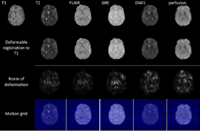

Multimodal Deformable Registration of Traumatic Brain Injury MR VolumesTime-efficient processing and analysis of magnetic resonance imaging (MRI) volumes is desirable for the neurocritical care and monitoring of traumatic brain injury (TBI) patients. An important problem of TBI neuroimaging data analysis is the task of co-registering MR volumes acquired using distinct sequences in the presence of widely variable pixel intensities that are due to the presence of pathology. Here we address this important and challenging problem using an implementation of multimodal deformable registration methods. One method have been implemented on graphics processing units (GPU). In this method we follow a viscous fluid model framework and replace mutual information with the Bhattacharyya distance as the measure of similarity between image volumes. The proposed algorithm is implemented on a GPU and its robustness is illustrated using a longitudinal multimodal TBI dataset. Another method proposes an extension to the principal axis transformation method for finding robust rigid transformation of two volumes. The additional elastic registration is based on a volume registration method MIND, proposed recently by Heinrich et al. More... | |